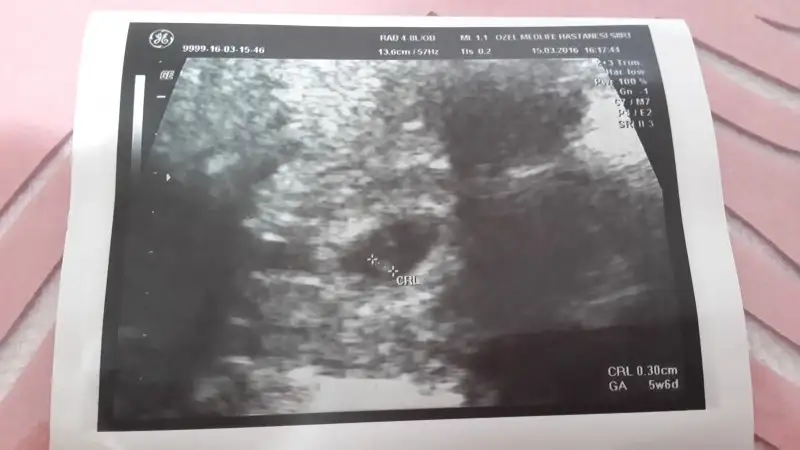

günaydın arkadaşlar benimde goruntume bakabilir misiniz bu resim 5 haftalıkkenCnm plasentanin yerine göre ve bebeğe gore yorum yapıyorum.

Burda 6 haftalık goruntusu hangisinde daha anlaşılırsa ona bakın istedim şimdiden tesekkurler